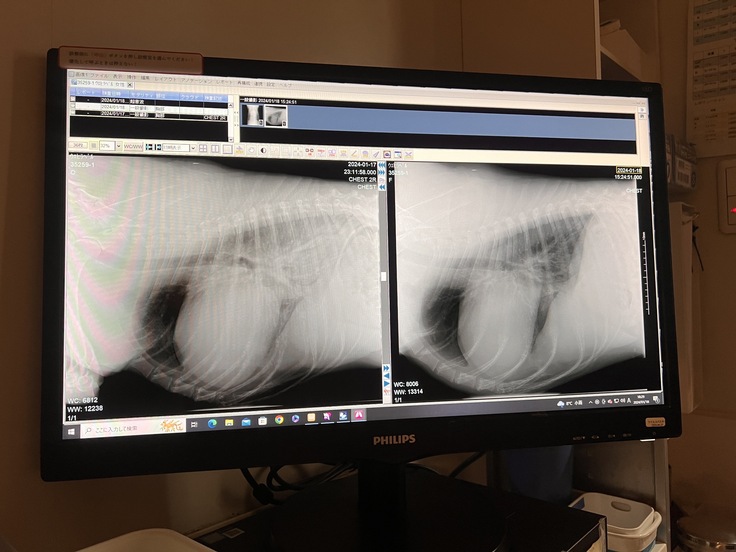

こちらの写真は、緊急入院をした日のレントゲン写真(左)と

酸素室に入れてもらい

24時間体制で点滴で利尿剤を入れ続けて

肺の水と心臓のうっ血がとりのぞかれた

次の日のレントゲン写真(右)です。

明らかに肺の白い影は無くなり

心臓の拡大も収まっており、

獣医師の先生も薬がよく効いてくれてるとおっしゃってました。